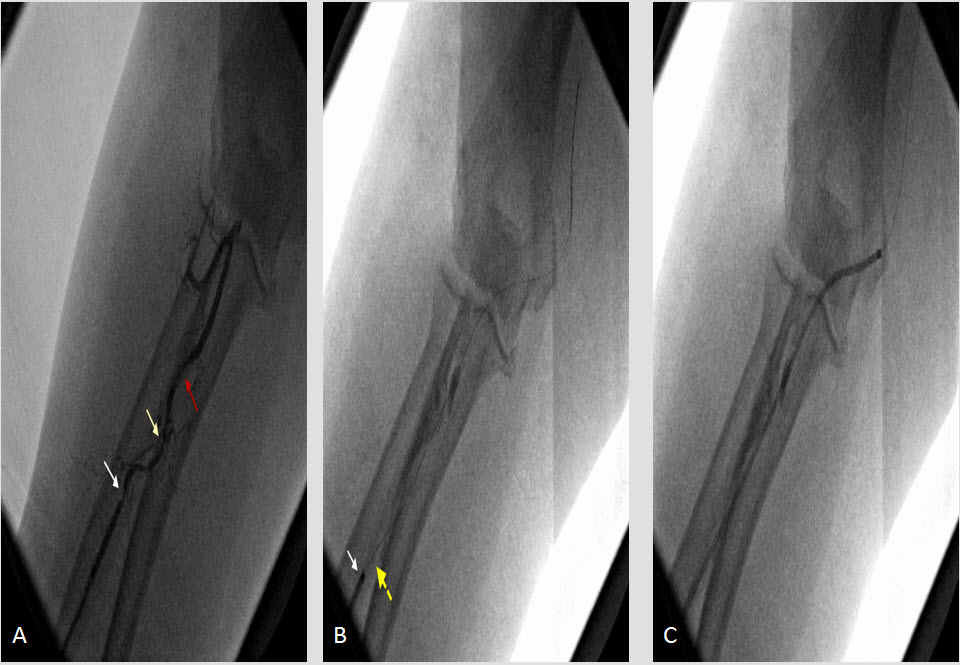

We present herein the case of a woman suffering from acute inferior myocardial infarction referred to our hospital for emergency catheterization after failed fibrinolysis and treated successfully with transradial rescue PCI. The case presentation is followed by a concise overview of data supporting the wider use of the radial approach, especially focusing on acute coronary syndromes.